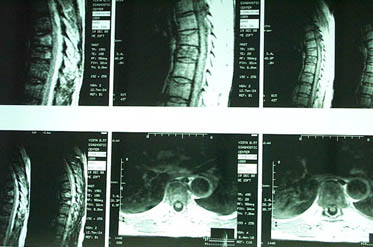

Уважаемые участники форума, Больной 53 лет, с жалобами на выраженные боли в области грудного отдела позвоночника, чувство онемения и стягивания в правой кисти, боли в мышцах конечностей и туловища. Отмечается парез правой верхней конечности.

В декабре 99 года перенес геморрагический а потом и ишемический инсульт левой задне-лобно-височной области. Выписался со значителсным улучшением неврологической симптоматики. Через год, на фоне обычного самочувствия, пожаловался на боль в спине, после чего появилось тоническое напряжение правой руки, половины туловища, перерастающее в приступ с судорогами по типутонико-клонических и потерей сознания. Госпитализирован. На CТ выявлен большой очаг в виде кистозной полости. Компрессионный перелом 8-9 грудных позвонков. В последующем, на протяжении полутора лет в общей сложности отмечено 5 аналогичных по формуле припадков. Падения с высоты во время приступов небыло. Также отрицает травмы позвоночника в анамнезе. ПовторнаяR-графия и СТ позвоночника выявила патологический компрессионный перелом и остеопороз тел Th 6; 7; 8; 9, (отрицательная динамика). Наличиенеобластомного процесса не выявлено. Все анализы, включая паратгормон, впределах нормы кроме:Са-Т - 2.66 (от 2.02 до 2.60)Р - 1.72 (от 081 до 1.62)СОЭ - 34мм/часСнимки 1, 2, 3, 4 прилагаются.Возникает ряд вопросиов: Может ли деструкция в левой задне-лобно-височной области быть связана с системним остеопорозм позвонков и пат. переломом? Моигут ли эпилптические приступы явиться причиной компрессионного переломапозвонков? Какие дополнительные исследования нужны для дифдиагностики болезни Куммелля? Тактика лечения (корсет?), показания и противопоказания к хирургическому вмешательству на позвонках в данной ситуации Прогноз?Буду благодарен любым соображениям,Аршак Мирзоян

imaging (MRI) may be able to do so. Materials and Methods: Patients

who underwent MRI evaluation for vertebral collapse were

retrospectively studied. Over a 21-month period from January 1995 to

September 1996, 47 patients with 58 vertebral collapses were studied.

Benign and malignant aetiologies were established by serial imaging,

clinical outcome and histology. Imaging was performed with T1 and

T2-weighted sequences, with contrast enhancement in some patients.

Collapsed vertebrae were examined for appearance of marrow on T1

and T2-weighted sequences and after contrast administration, signal

intensity of adjacent discs, degree of marrow involvement, involvement

of posterior elements, presence or absence of paraspinal mass and

end-plate integrity. Agreement between the final and radiological

diagnosis was evaluated. Results: There were 36 benign vertebral

collapses (20 osteoporotic, 7 post-traumatic, 9 infective) and 22

malignant ones (20 metastatic carcinoma, 2 multiple myeloma). Features

which pointed t o malignant cause were hypointense marrow on

T1-weighted images, marrow enhancement after intravenous contrast,

greater than 50% marrow involvement and involvement of posterior

elements. Of the vertebral collapses due to infection, 78% showed

end-plate disruption. Conclusions: This study shows that MRI can be

used to accurately differentiate between benign and malignant causes

of vertebral collapse. Further differentiation between an

osteoporotic, traumatic or infective cause can be done with the help

of clinical history and evaluation of end-plate integrity.

Ann Acad Med Singapore 2002; 31:8-14